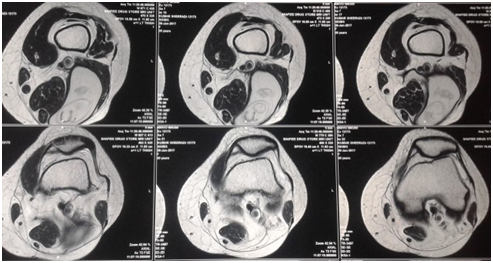

A 30 year old married female with no known comorbidity presented with a throbbing pain of moderate to severe intensity in left thigh and popliteal fossa region. On physical examination there was a tender erythematous, fluctuant swelling on posterior aspect of distal thigh and popliteal fossa. Incision and drainage of Abscess was done in one of the local hospitals and about 1.5 L of frank pus was drained. As per the records available with the patient. Pus contained some whitish membranes and cysts. Histopathological examination of specimen was done which revealed lamellated membranes of Echinococcus granulosus. No post-operative medical therapy was prescribed at that time. After a period of about one year the lady again presented to Sheri Kashmir Institute of medical Sciences Soura Srinagar with gradually increasing painless swelling in distal one third of thigh posteriorly. Ultrasonography of left thigh swelling was done which showed evidence of 10x4.7x6.2cm, thick walled cyst with finger-like projections and daughter cysts in lower third of posterior thigh with surrounding fat stranding, suggestive of hydatid Cyst. Screening ultrasonography of liver and spleen showed no cystic lesion. Chest Radiography was also found to be normal. MRI of Left lower thigh showed fluid intensity collection or cyst between Biceps femoris and semitendinosus myo-fascial planes which was extending deep to semitendinosus muscle. The swelling was 9.1x6.3x5.5cm and showed hypointense intracystic septae or crumpled membranes. Mild hypointense signal on T1W images and bright signal on STIR and T2W images was seen,suggestive of infected Hydatid Cyst. Hydatid Serology of the patient was found to be positive. Patient was put on oral Albendazole 400mg for 2 weeks and then excision of cyst was done. Albendazole was continued postoperatively for 4 weeks (Figure 1), (Figure 2).

Figure 1 MRI showing hypointense cystic lesion in left lower thigh.